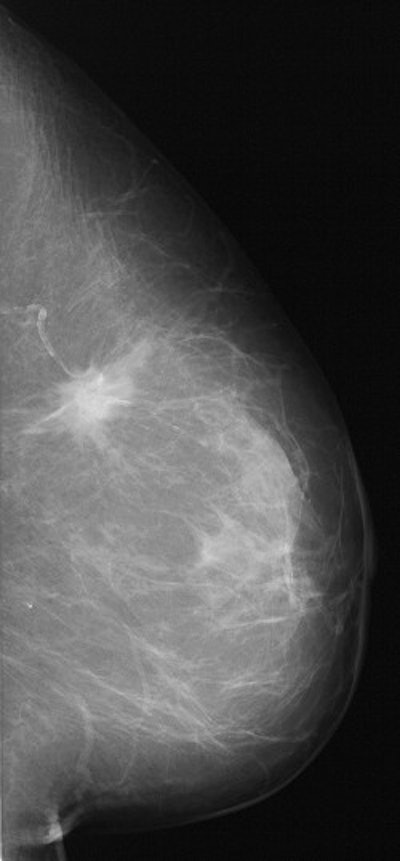

DSPM images acquired on the Mammomat 3000 Nova, including zoom (middle) and spot magnification (below). Images courtesy of Dr. Wolfgang Matzek.